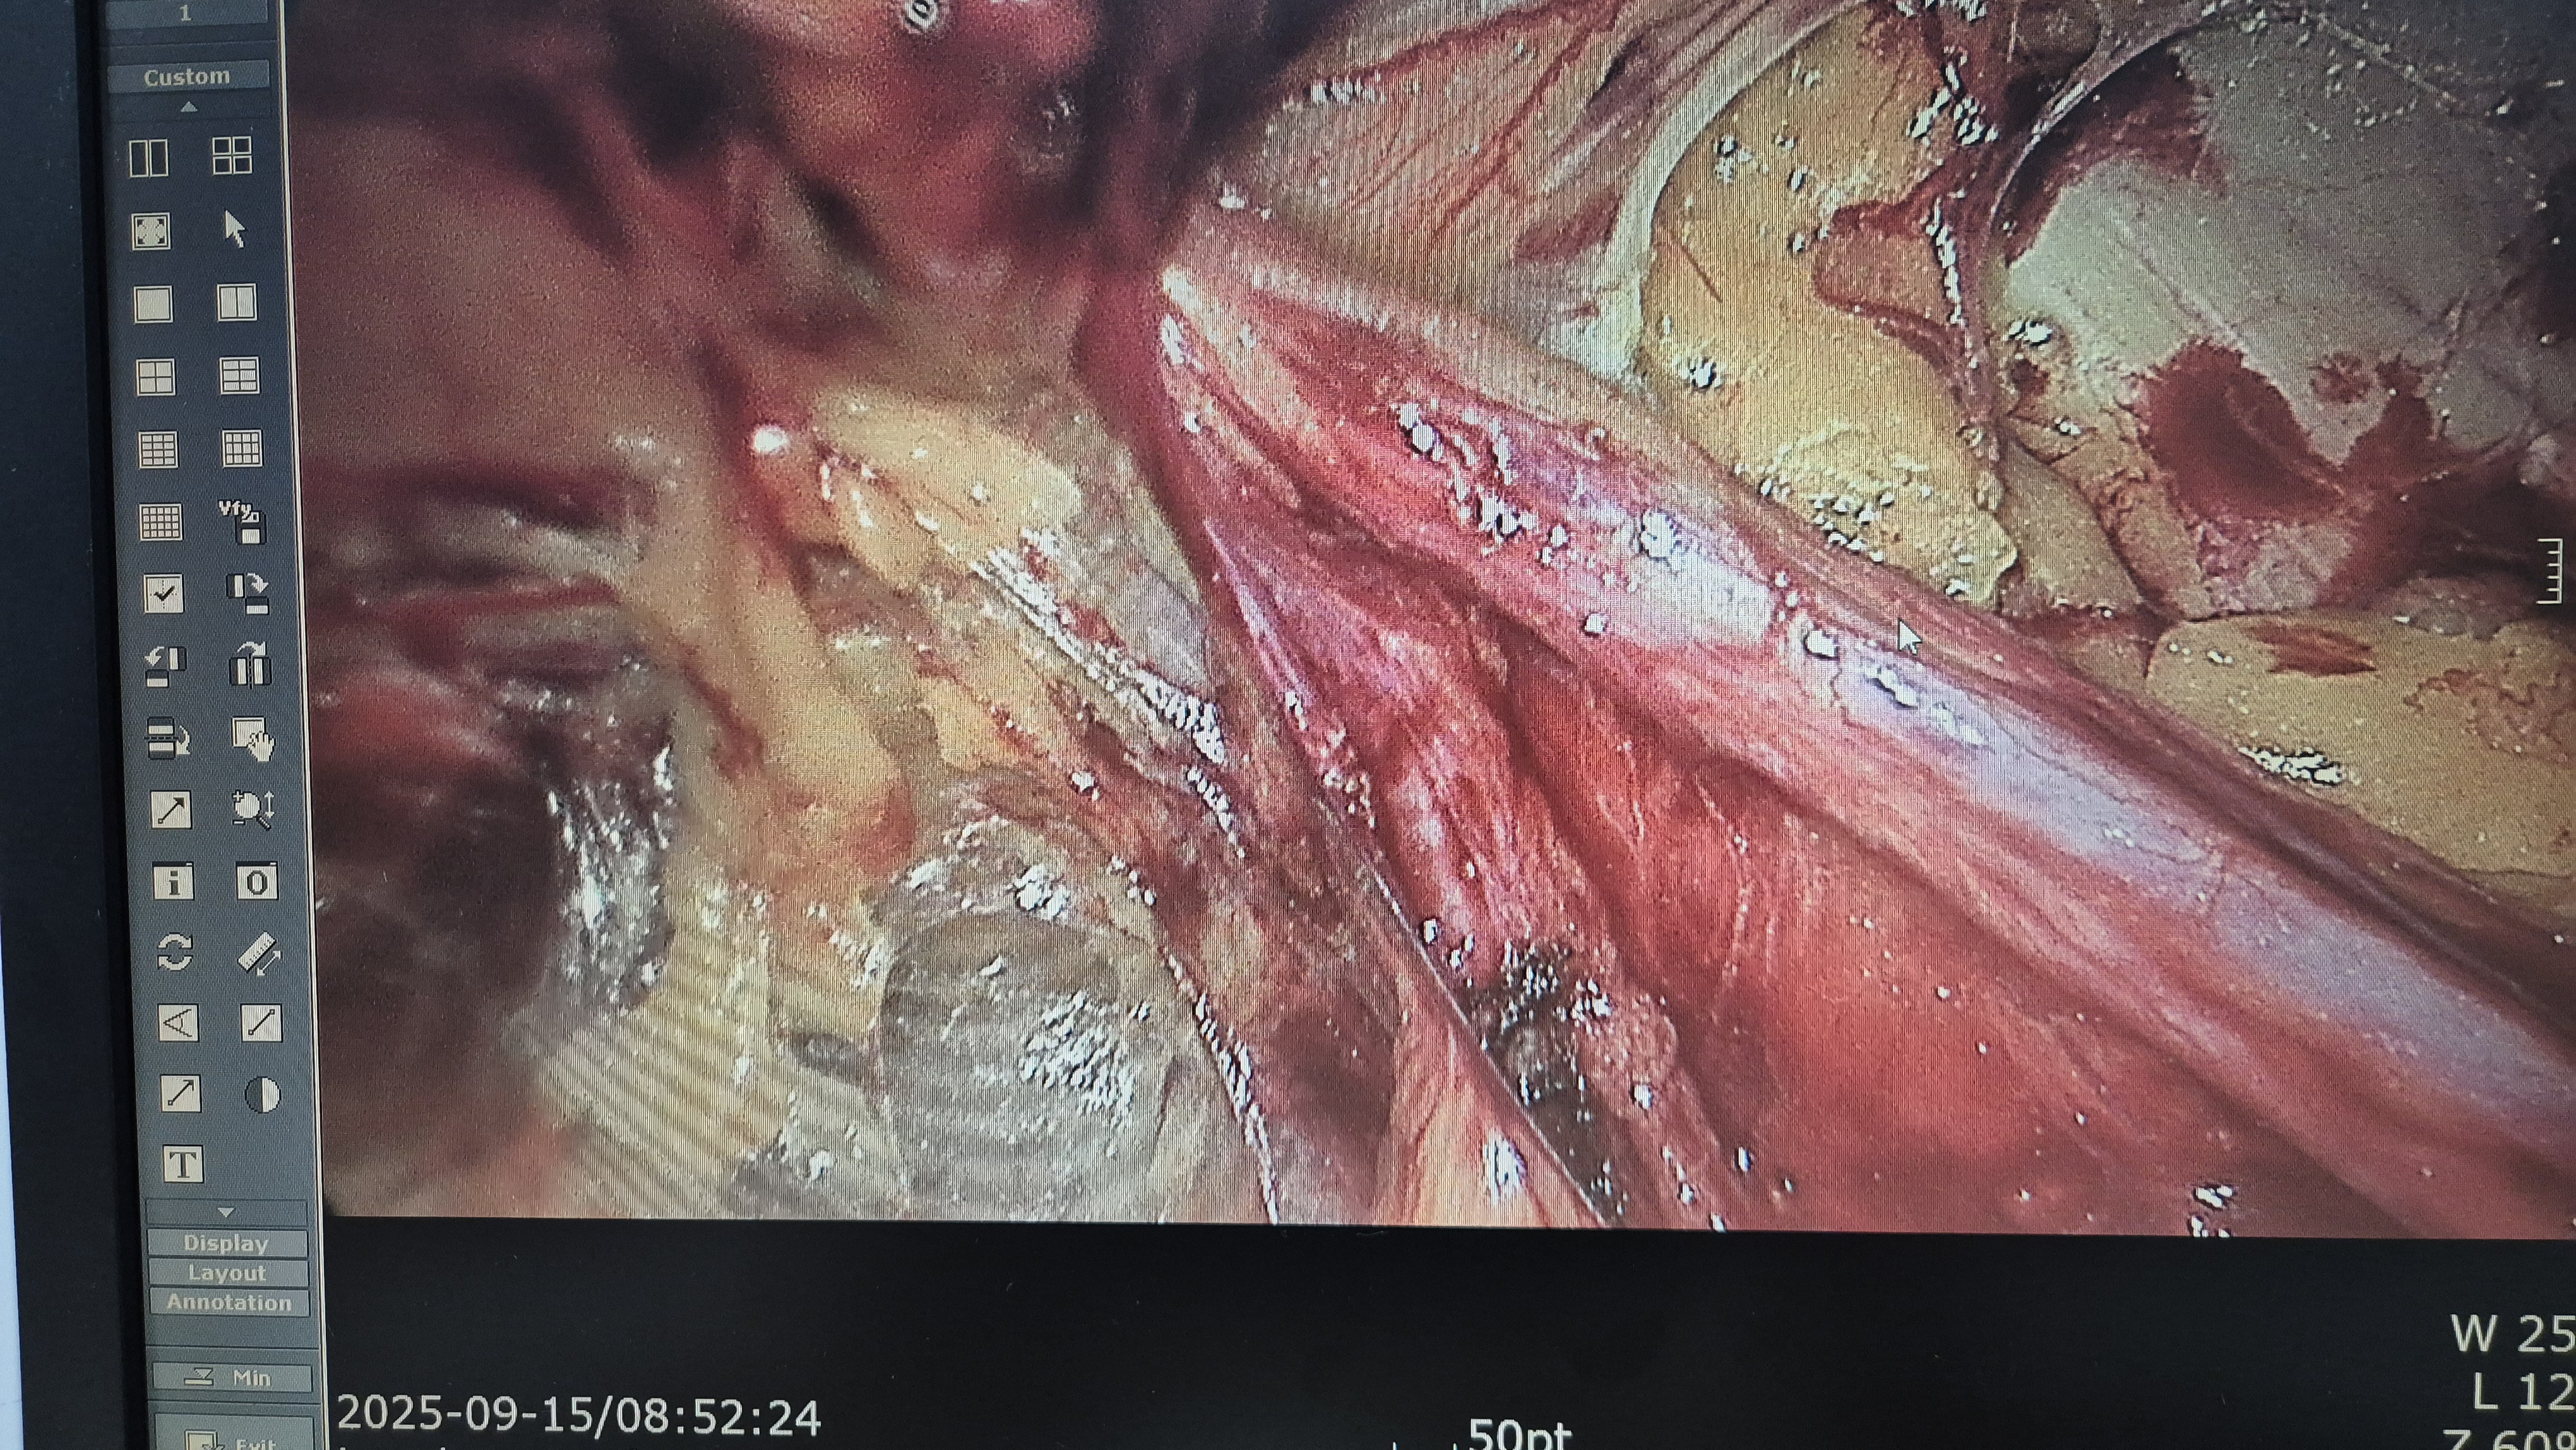

메쉬로 보강.